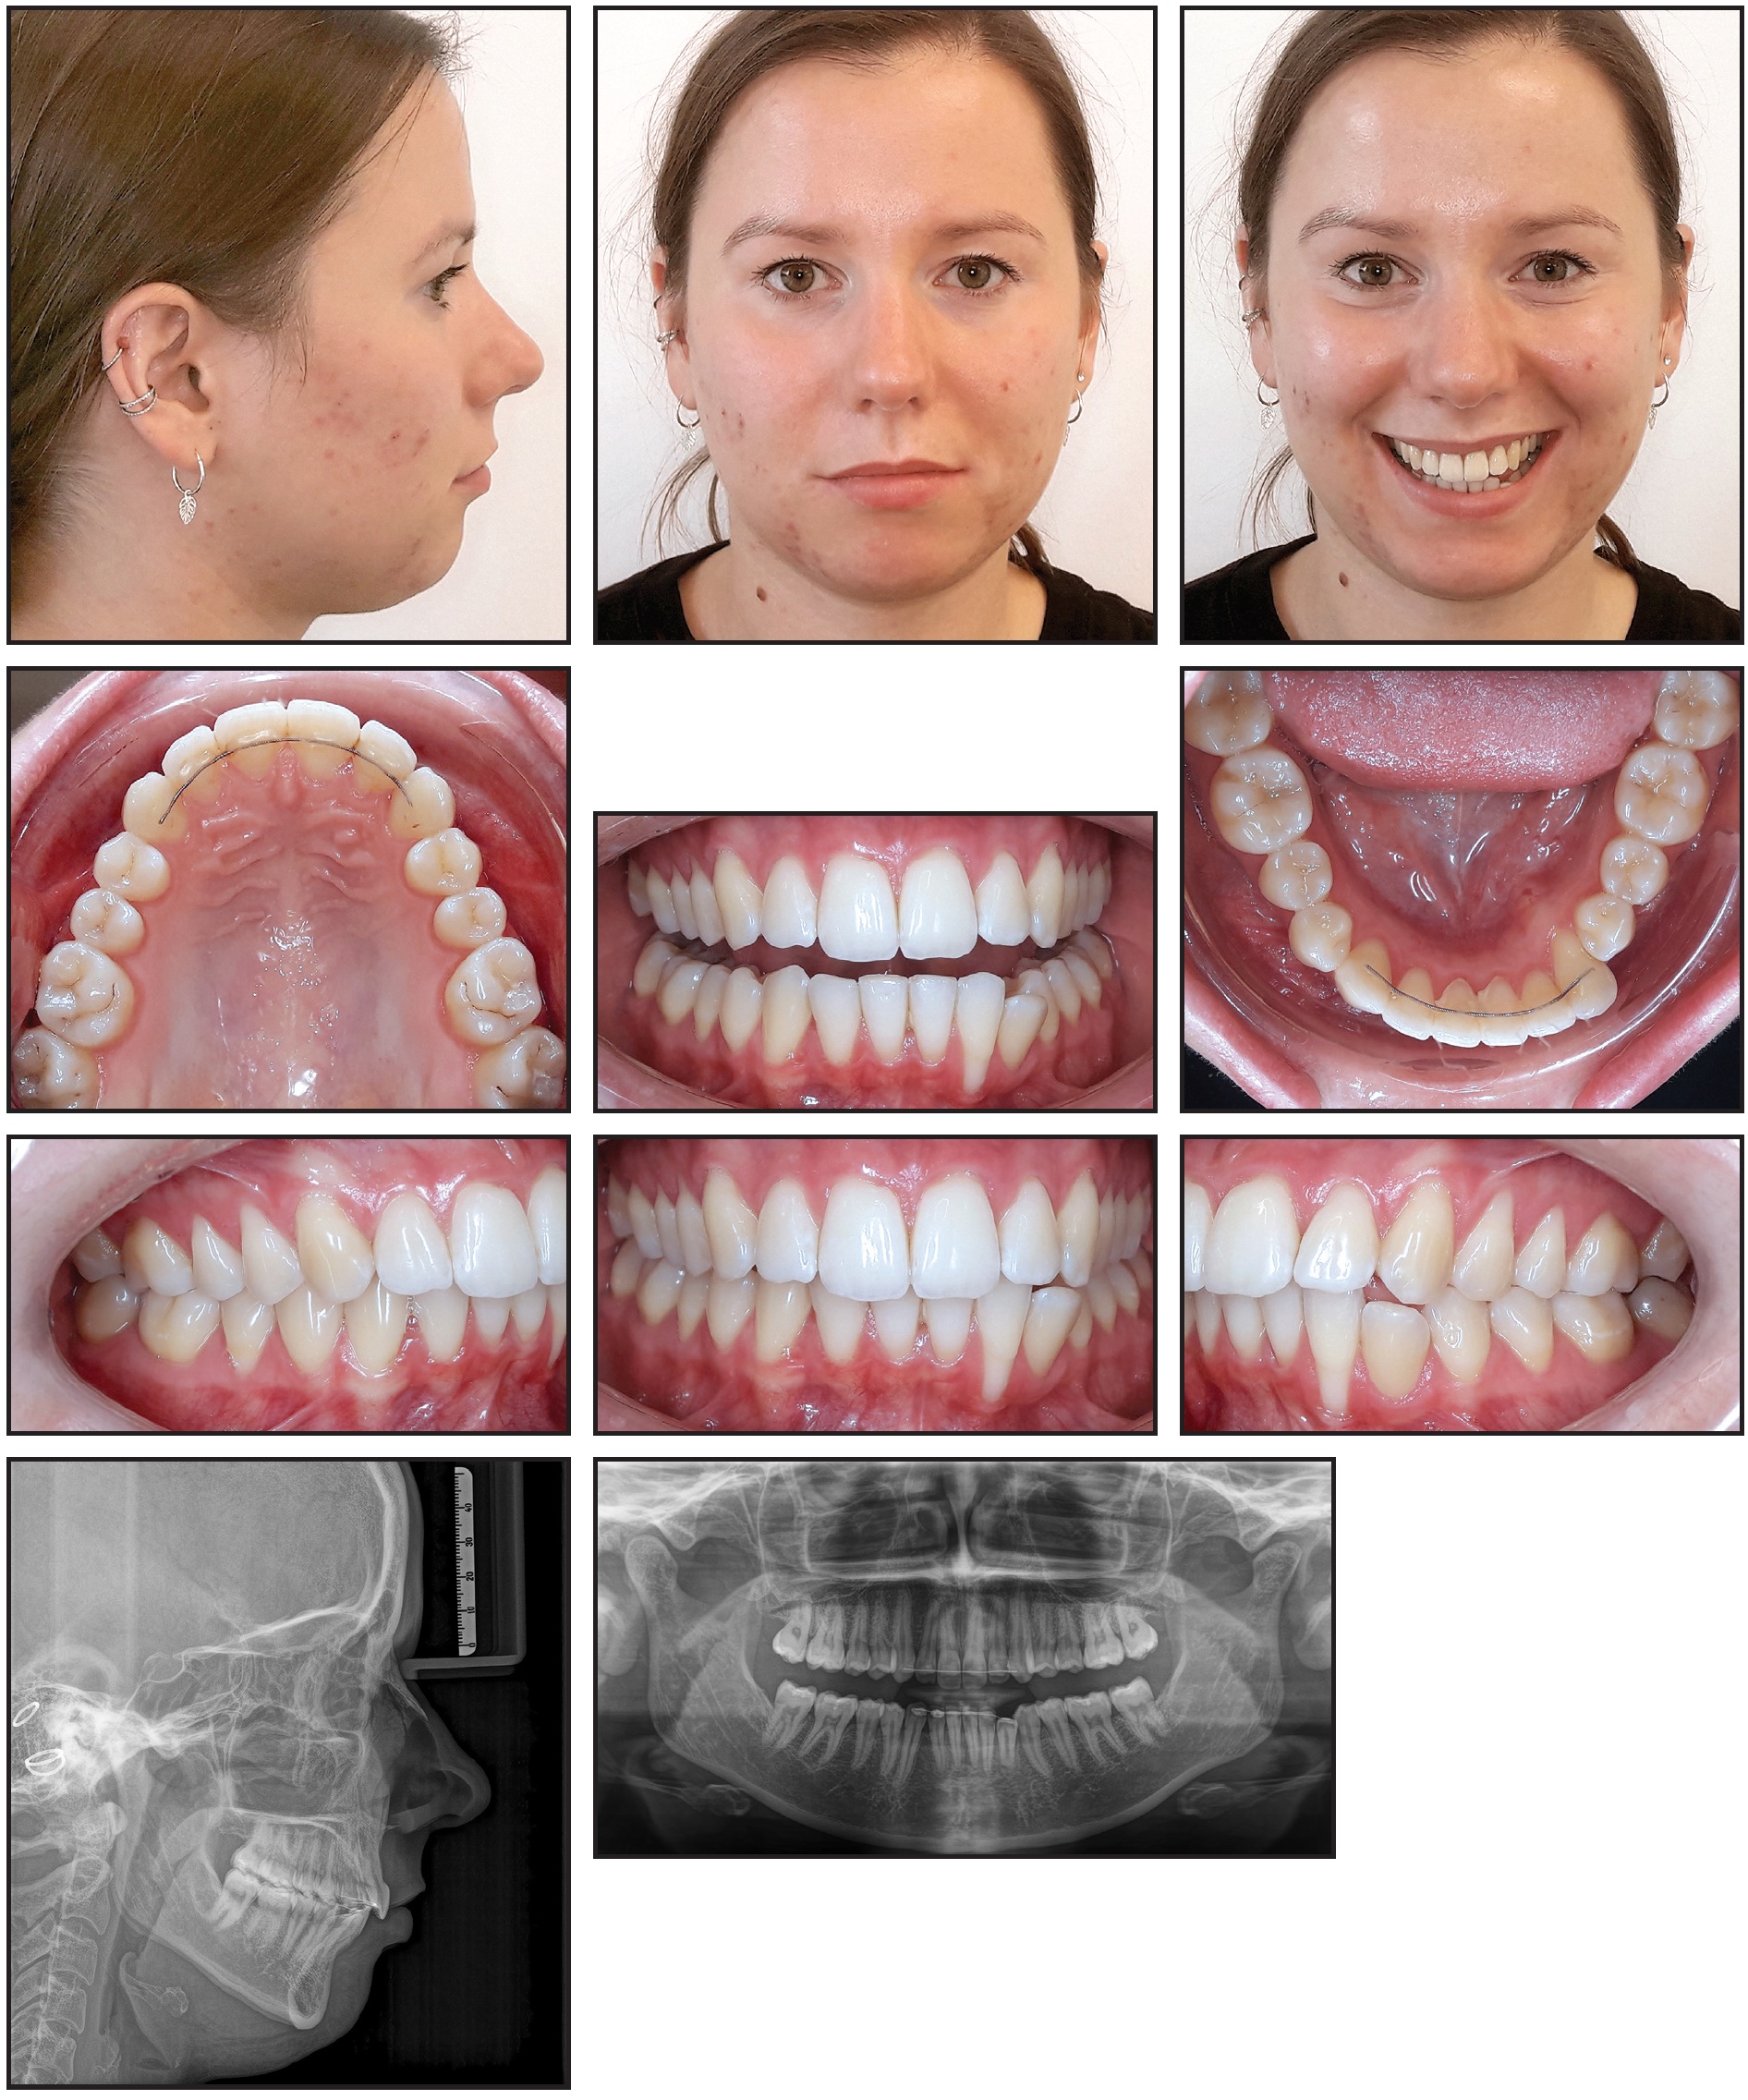

A removable retainer was delivered for two months of wear, after which a lower 3-3 Nitinol CAD/CAM Memotain† lingual retainer wire was bonded (Fig. 5).

Fig. 5 About eight months after beginning of treatment, with bonded lower 3-3 Memotain† lingual retainer wire in place.

The protrusion of the lower left incisors and proclination of the lower left canine were corrected, realigning the lower arch and closing the open bite. Controlled lingual tipping of the lower left lateral incisor reduced the depth of the gingival recession from 5mm to 3.5mm and significantly decreased its width. No complications were noted, and the patient was satisfied with the esthetic results. Cephalometric analysis revealed no clinically significant sagittal or vertical changes (Table 1).